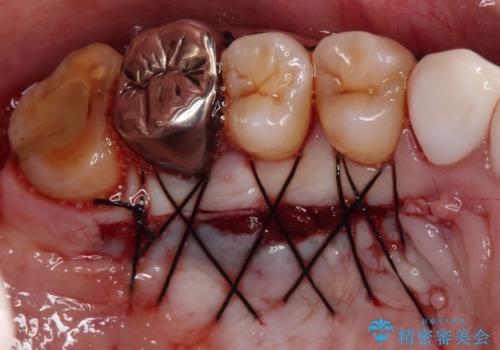

- 今まで知覚過敏の薬や歯磨き粉などを散々試しても全く改善されないとのことで来院された患者様です。

歯根面が露出しており、少し風をかけるだけでもしみてしまう状況でした。

セラミッククラウンによる治療も検討されていましたが、歯肉が非常に薄く、クラウンを装着しても将来的に歯肉退縮を起こす可能性が考えられたので、まずは歯肉移植による根面被覆を行うこととしました。

外科処置に恐怖心があるとのことで、移植手術を行う際には、静脈内鎮静法にてリラックスした状態で処置を受けていただきました(別途税別5万円)。